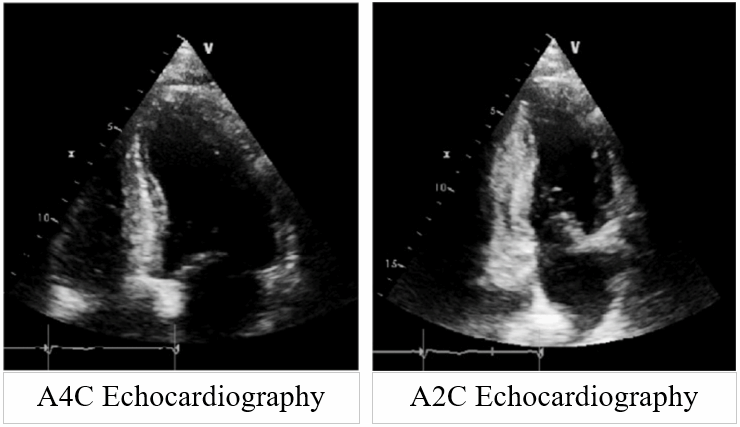

论文以 HMC-QU 数据集为实验平台,该数据集包含来自130名受试者的260张超声图像,覆盖两种标准视图(A2C 与 A4C),如图1所示,是目前公开可用、面向心肌梗死(Myocardial Infarction, MI)检测的超声数据集之一。

图1:心脏各腔室在 A2C 和 A4C 视图中的超声心动图显示